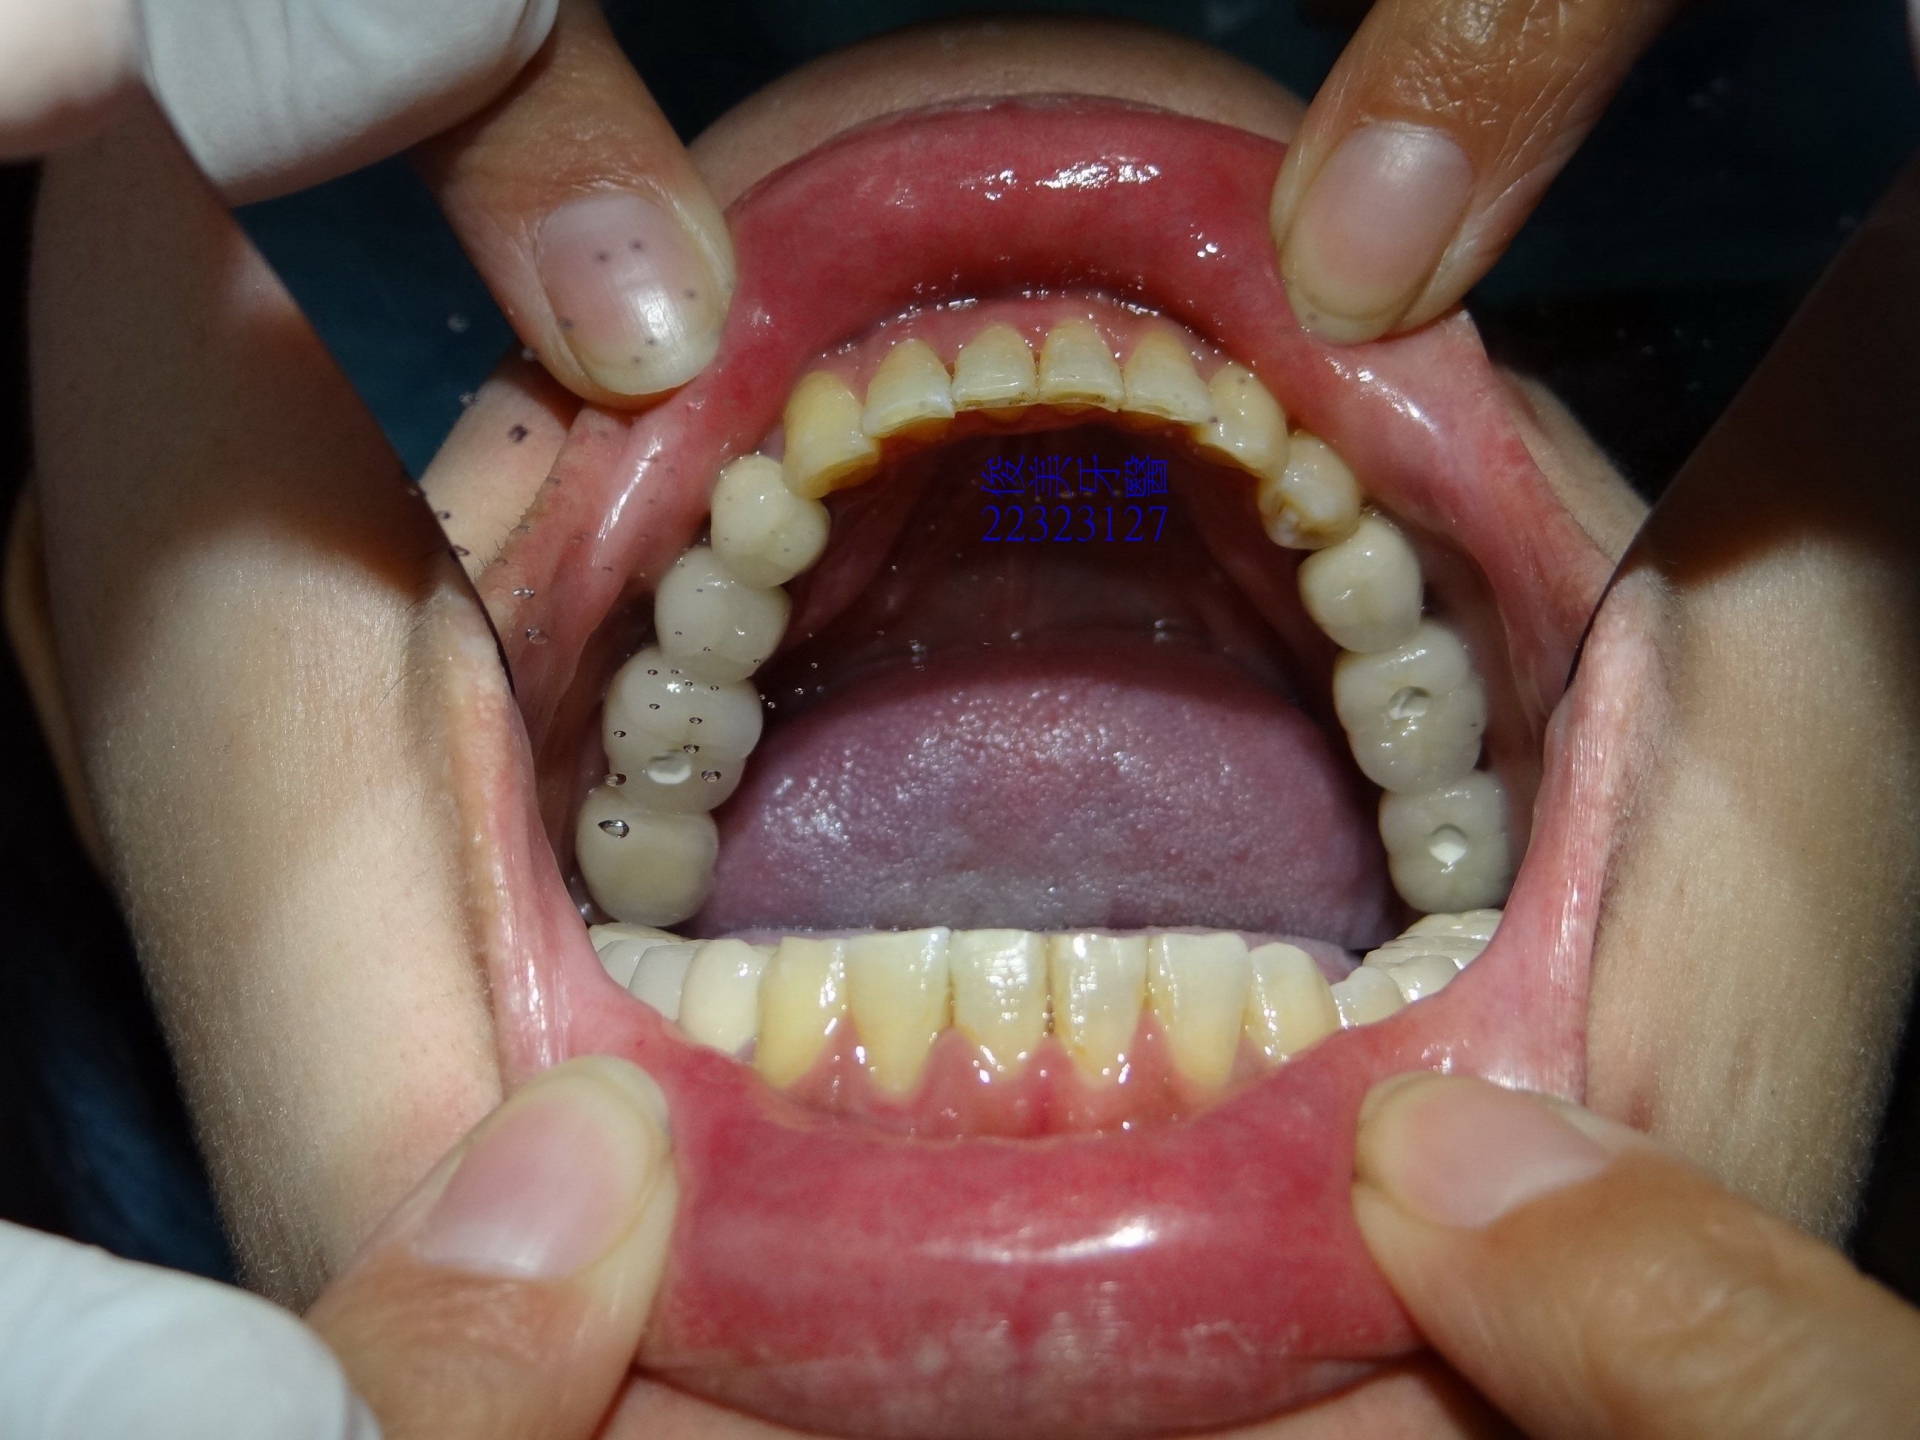

下排牙齒後牙因空間不足,採金屬牙修復,牙橋不易清潔。

下顎狀況。